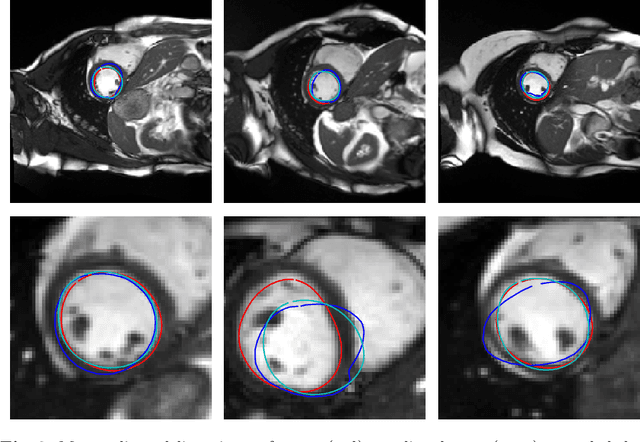

Abstract:Surface reconstruction is a vital tool in a wide range of areas of medical image analysis and clinical research. Despite the fact that many methods have proposed solutions to the reconstruction problem, most, due to their deterministic nature, do not directly address the issue of quantifying uncertainty associated with their predictions. We remedy this by proposing a novel probabilistic deep learning approach capable of simultaneous surface reconstruction and associated uncertainty prediction. The method incorporates prior shape information in the form of a principal component analysis (PCA) model. Experiments using the UK Biobank data show that our probabilistic approach outperforms an analogous deterministic PCA-based method in the task of 2D organ delineation and quantifies uncertainty by formulating distributions over predicted surface vertex positions.